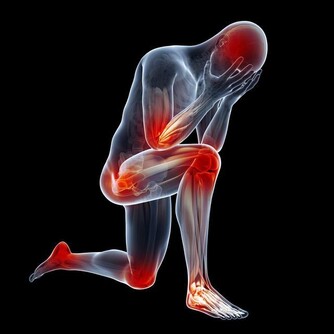

(3) 壓迫症狀,當腫瘤向周圍組織浸潤或壓迫神經時,可引起腹痛、腰痛或坐骨神經痛,若壓迫盆腔靜脈,可出現下肢浮腫;巨大的腫瘤可壓迫膀胱,有尿頻、排尿難、尿瀦留;壓迫直腸則大便困難;壓迫胃腸道便有消化道症狀;壓迫膈肌可發生呼吸困難,不能平臥。

(5)疼痛,因癌腫轉移而出現相應的症狀,卵巢惡性腫瘤極少引起疼痛,如發生腫瘤破裂、出血或感染或由於浸潤壓迫鄰近臟器可引起腹痛、腰痛。